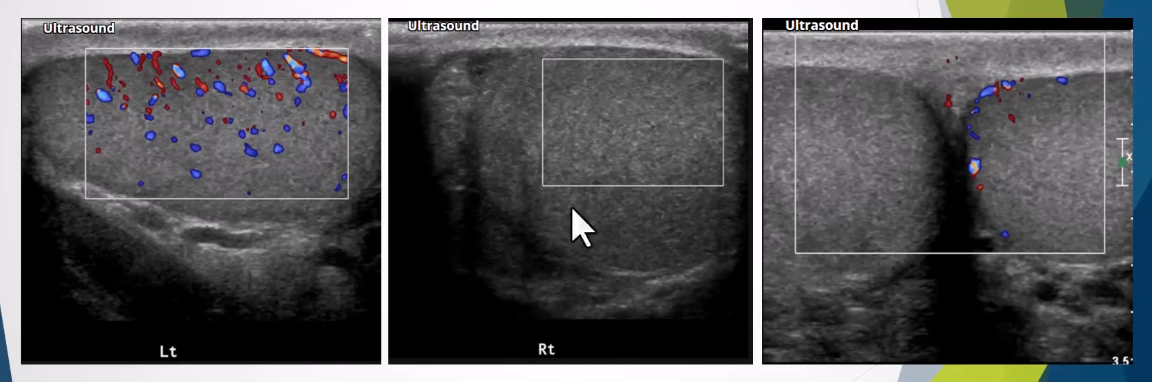

Altered Blood Flow:

Intratesticular arteries characteristically have a low resistance pattern with a mean resistive index of 0.62 (range 0.48 - 0.75)

Incomplete torsion - reversal of distolic flow and RI >0.75

Complete torsion - absence of blood flow in both the testis and epididymis

.